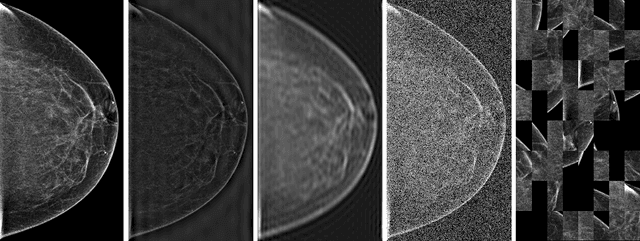

Deep neural networks (DNNs) show promise in breast cancer screening, but their robustness to input perturbations must be better understood before they can be clinically implemented. There exists extensive literature on this subject in the context of natural images that can potentially be built upon. However, it cannot be assumed that conclusions about robustness will transfer from natural images to mammogram images, due to significant differences between the two image modalities. In order to determine whether conclusions will transfer, we measure the sensitivity of a radiologist-level screening mammogram image classifier to four commonly studied input perturbations that natural image classifiers are sensitive to. We find that mammogram image classifiers are also sensitive to these perturbations, which suggests that we can build on the existing literature. We also perform a detailed analysis on the effects of low-pass filtering, and find that it degrades the visibility of clinically meaningful features called microcalcifications. Since low-pass filtering removes semantically meaningful information that is predictive of breast cancer, we argue that it is undesirable for mammogram image classifiers to be invariant to it. This is in contrast to natural images, where we do not want DNNs to be sensitive to low-pass filtering due to its tendency to remove information that is human-incomprehensible.